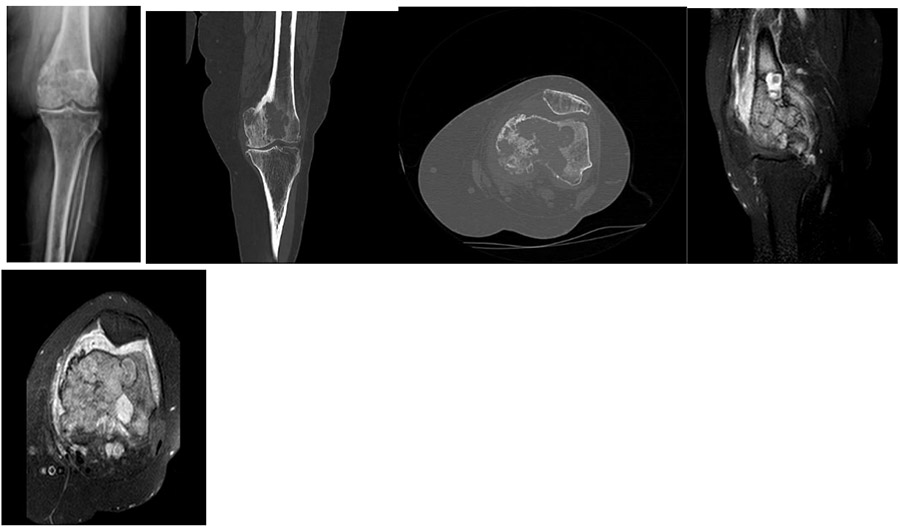

CASE 44: Lung cancer metastasis to the lower end of the left thigh (femur).

Before the surgery: X-ray and CT scans show metastatic lesions and significant damage; MRI reveals tumor tissue filling the lower part of the femur and extending beyond the bone, accompanied by surrounding edema.